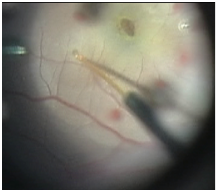

All surgeries described were performed by the same surgeon (ER). A 23 gauge, 3-port pars plana vitrectomy (PPV), with induction of a PVD (if incomplete), internal limiting membrane (ILM) peel after staining with Brilliant Peel(R) (Geuder, Germany), posterior pole detachment with sub-retinal fluid injected via 41G needle, fluid-air exchange, and gas tamponade with short-acting 30% sulphur hexafluoride (SF6) gas was performed. Fluid was left to slowly absorb postoperatively.

The ILM was peeled in six of seven cases to a size of at least 1.5 disc diameters from the foveal centre. In the case of the FTMH after macula-off RRD the ILM had already been peeled at the first attempt to close the hole. Induction of PVD was required in six cases. In all the cases, the Retina Expansion method was adopted to assist closure of the FTMH. The technique involved injecting balanced salt with the viscous fluid injector via a 41 gauge sub-retinal cannula into the perifoveal region (>500um from foveal centre). In each case multiple sites in the para fovea were injected with balanced salt to induce a posterior pole detachment. There was no massaging of retina as has been described previously 13. The fluid air exchange at the end of the procedure allowed all the multiple injection sites to coalesce into a confluent detachment of the posterior pole. Patients were advised to posture sitting up and leaning forward for a period of 7 days post operatively (Figure 1&2).

Figure 1 Still from video demonstrating parafoveal injection of balanced salt using 41 gauge sub-retinal cannula.

Figure 2 Still from video demonstrating posterior pole detachment completed.